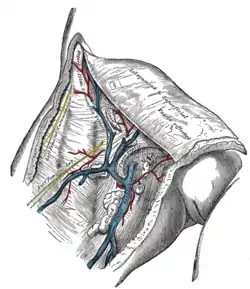

The great saphenous vein and its tributaries at the fossa ovalis.

The great saphenous vein and its tributaries at the fossa ovalis. The femoral vein and its tributaries.